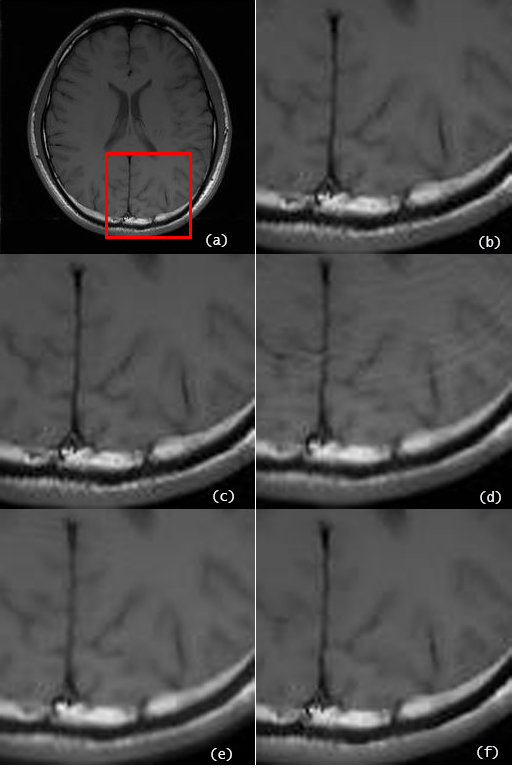

For the brain data set, the reconstructed images by the proposed algorithm using undersampled -space data of nominal reduction factor, and higher and are shown in Fig.2 (b), (c) and (d), respectively, in comparison with the SOS image using the full space data in Fig.2 (a). For the brain date set of , Fig.3 presents the reconstructed image by the proposed method in comparison with that by other recent algorithms, which are IRGN-TGV [7], SPIRiT [4] and Sparse-BLIP [8]. To provide more detailed reconstruction information for comparison, a selected area of each reconstructed image by different algorithms is zoomed and displayed in Fig. 4.

The NMSEs of the reconstructed brain images of different algorithms are listed in Table I for , respectively. The results clearly show that the proposed convex optimization method outperforms other methods in terms of the reconstruction accuracy at high undersampling rates as well as reduction of artifacts.